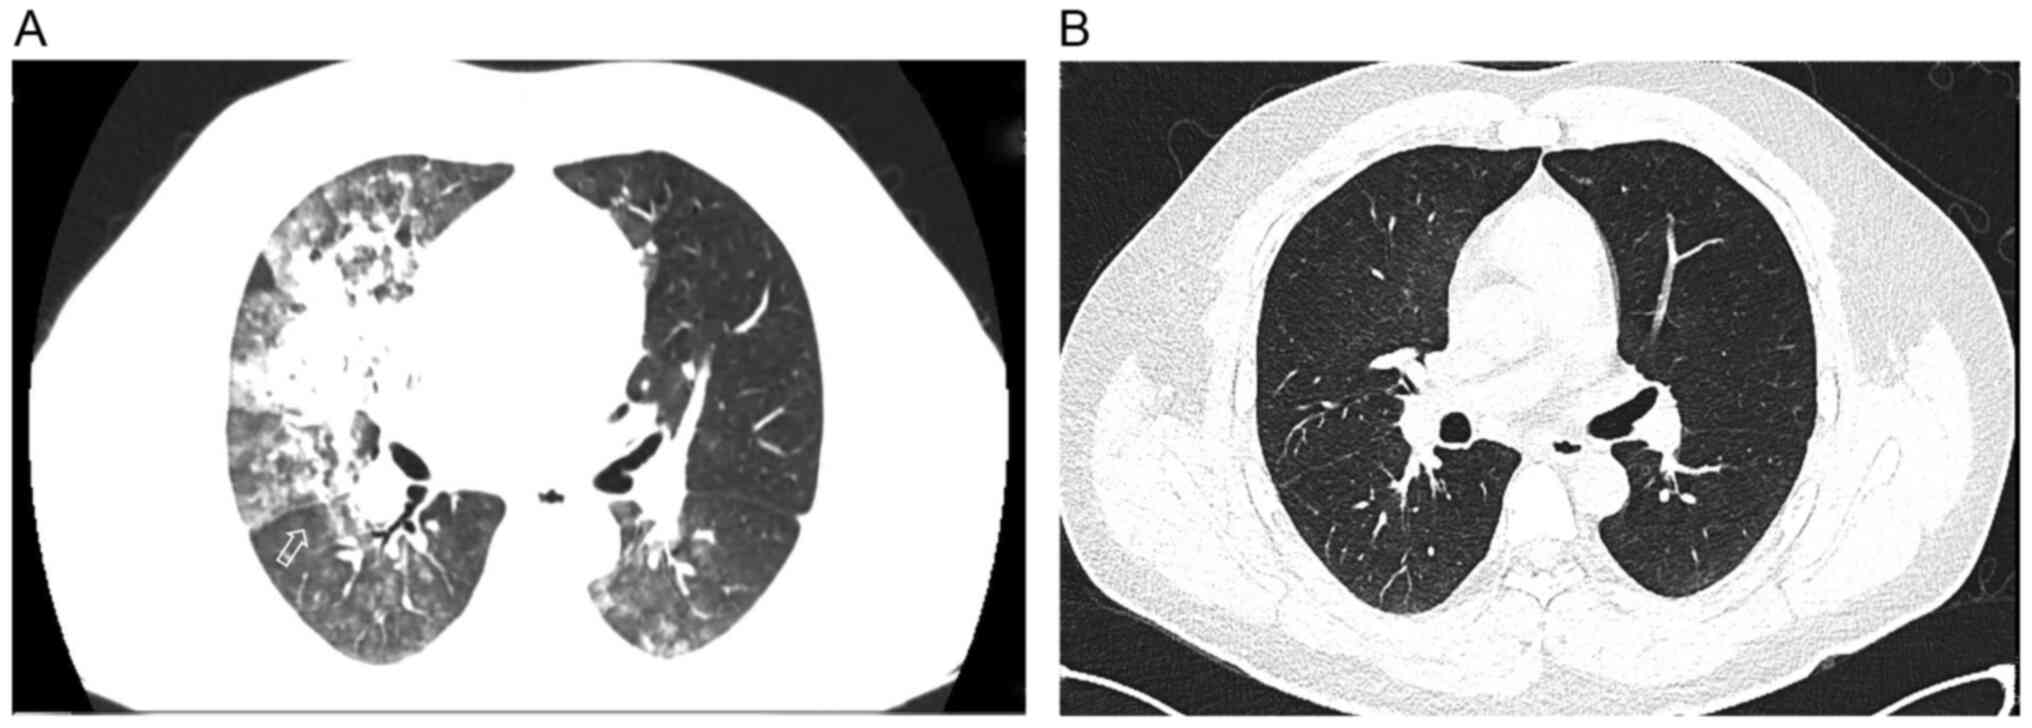

Figure 3

Chest CT of Case 3. (A) CT scan performed on arrival to the Emergency Department ~1 h after aspiration showed bilateral diffuse exudative shadows and right upper lobe consolidation. (B) CT scan performed on the fifth day after treatment showed resolution of most of the interstitial opacities. The arrows represent exudative changes in the lungs.

In January 2022, a 33-year-old man fell into a pool. First-aid paramedics arrived soon after and transferred him to the Tongji Hospital (Wuhan, China) for further treatment. The paramedic crew observed that he had aspirated gastrointestinal contents and provided suction care. Upon arrival at the emergency department, the patient had fully revived but developed mild dyspnea with RR, 26 breaths/min and SpO2, 92%. ABG test results were as follows: pH 7.335; PaO2, 59 mm Hg; PaCO2, 508 mmHg; SaO2, 93%; and P/F, 169. Although no remarkable abnormalities were found upon physical examination, the patient was admitted to the ICU owing to severe bilateral alveolar exudation (Fig. 3A) and manifestations of dyspnea. The patient was diagnosed with chemical pneumonitis, pulmonary infection and ARDS according to the 2013 Berlin Definition (8).

Considering the experience with the treatment protocol presented in the two prior cases, nasal high-flow oxygen (oxygen flow 40 l/min; oxygen concentration 50%), ceftazidime 2 g every 12 h and sivelestat sodium (0.1 g three times/day using an intravenous pump for 7 days) were administered to the patient under significant pulmonary exudation early in the onset of the disease (within 24 h) and mild ARDS diagnosis (although the P/F of the patient was 314 mmHg under high-flow nasal cannula oxygen administration, the P/F of the patient was only 169 mmHg under nasal cannula oxygen administration), according to the aforementioned drug indications. Methylprednisolone was not used because of mild dyspnea and the presence of inhaled gastric contents. The patient had no pre-existing COPD or other illnesses, and high-flow oxygen was used solely for respiratory support and not for any therapeutic role. After 5 days, the ABG results had improved, showing PaO2, 157 mmHg; PaCO2, 30.7 mmHg; SaO2, 100%; and P/F, 314. Additionally, chest CT showed a significant improvement (Fig. 3B). The symptoms improved in the course of 7 days and the patient was subsequently discharged.